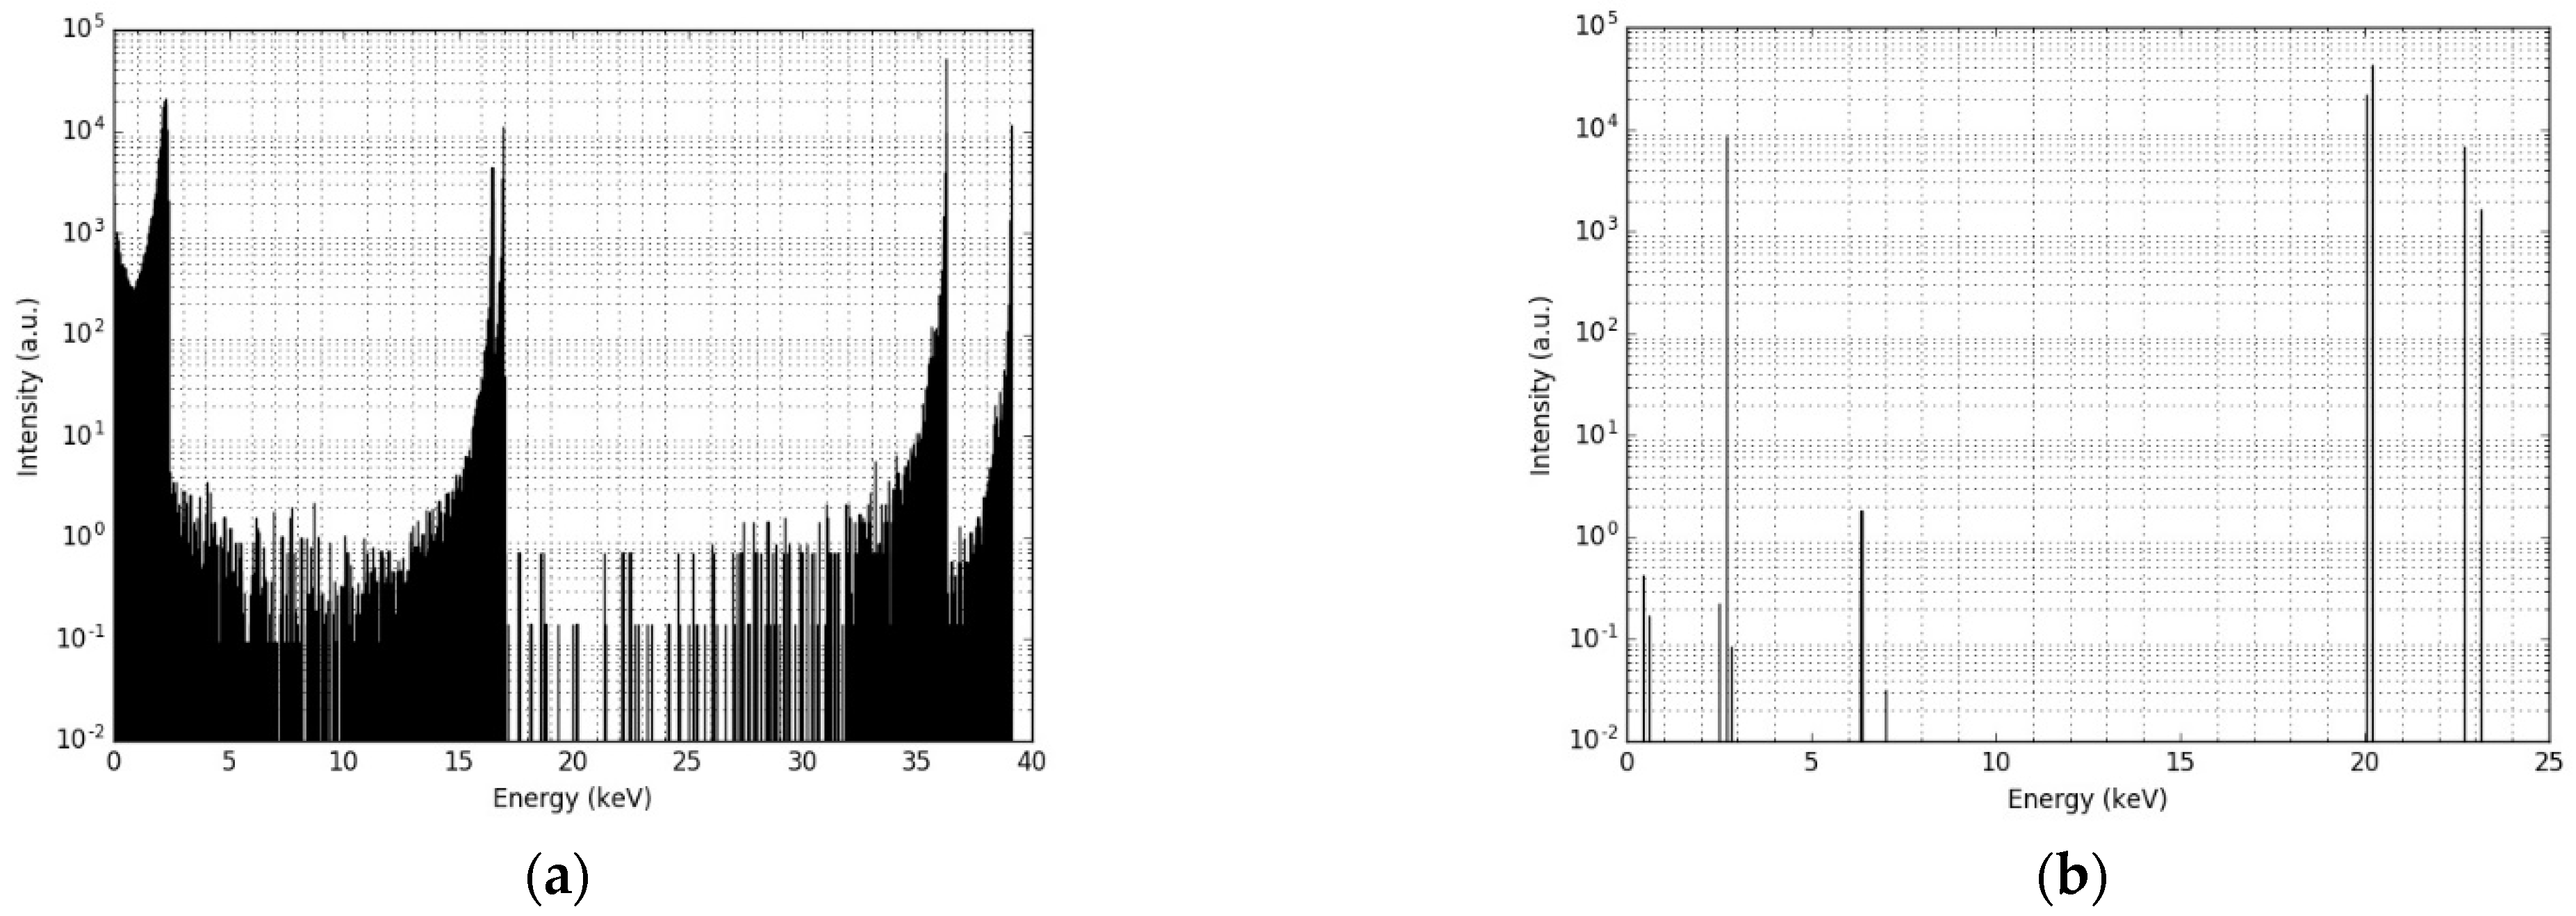

3.1. Single Nanoparticle Energy Spectra

3.2. Radioactive Magnetic Nanoparticle (RMNP) Seed